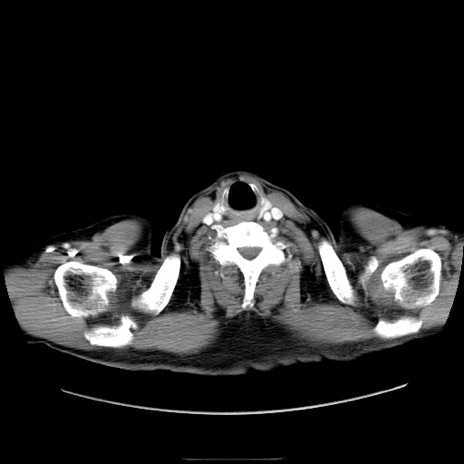

冠状断像